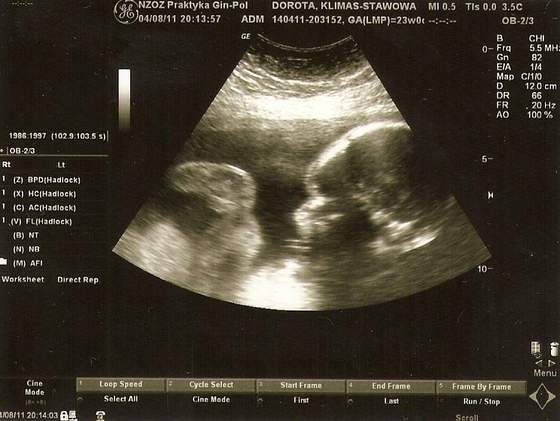

Narazie nic nie robię tylko próbuję dodzwonić się do gina ale on nie odbiera. Kuźwa kasę to wie ile wziąć ale tel. odebrać nie potrafi. Coś czuję że jak się do niego nie dodzwonię to mąż mnie sam wywiezie na IP dziś.![]()

Kochana musisz wiedziec co i jak-ważne żebyś była zdrowa Ty i maluszek. Jeśli się do niego nie dodzwonisz to jedz na IP niech zobaczą co Ci jest. Będziesz spokojniejsza Ty i otoczenie w tym ja

Nie możesz czekać dłużej żeby później nie żałować.